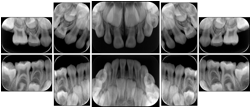

Intra-oral radiography typically involves acquisition of multiple images of various parts of the dentition. Many digital radiographic systems offer customized templates that are used for displaying the images in a study on the screen. These templates may also be referred to as mounts or view sets. The Structured Display Object represents a standard method of encoding and exchanging the layout and intended display of Structured Displays. A structured display object created in this manner could be stored with a study and exchanged with images to allow for complete reproduction of the original exam.

3. A dental provider wishes to capture a series of DICOM IO images for the patient’s dentition. The tooth morphology, teeth are divided into molars, premolars, canines and incisors, and a number of images for each jaw. The anatomic information was captured utilizing the triplet of schema. This standard code sequence is based on ISO 3950-2010, Dentistry - Designation system for teeth and areas of the oral cavity.

Every IO image should have anatomic information either through the primary or modifier sequence.

In most standard cases, images are oriented in structured layouts. These structured displays are useful to be shared between providers for reference purposes.

Table OO.1.1-1 shows structured display standard templates, where Viewset ID is based on the Japanese Society for Oral and Maxillofacial Radiology (JSOMR) classification provided by JIRA (Japan Medical Imaging and Radiological Systems Industries Association, www.jira-net.or.jp). Expected or typical teeth to be imaged location, region and designation codes are based on ISO 3950-2010, Dentistry - Designation system for teeth and areas of the oral cavity. For all the hanging protocols listed in OO.1.1-1, the value to use for Hanging Protocol Creator (0072,0008) is "JSOMR" and the value to use for Hanging Protocol Name (0072,0002) does not include "JSOMR" (e.g., "DL-S001A", not "JSOMR DL-S001A").